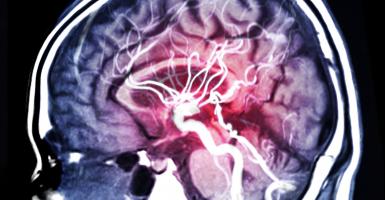

AVC : La réadaptation cardiaque "marche" aussi

AVC : Preuve d’efficacité d'une neurorégénération par thérapie génique

Actualité publiée le 26/09/2020AVC du NOUVEAU-NÉ : Le rôle clé de la microglie

COVID-19 : Un facteur indépendant de risque d’AVC

COGNITION : Pourquoi diabète et AVC forment un cocktail particulièrement mauvais

AVC : Le médicament qui réduit le gonflement cérébral

Actualité publiée le 24/02/2020AVC : Le médicament qui prolonge la survie des neurones